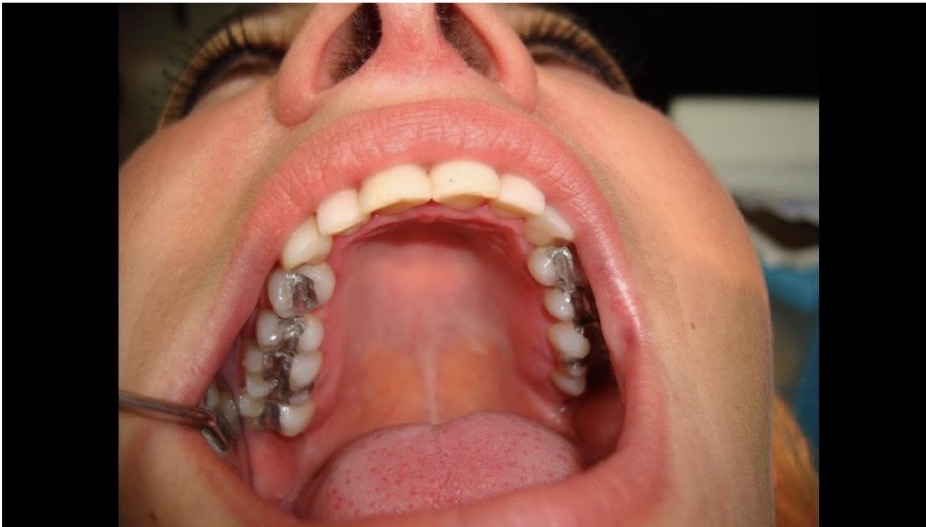

BN CÓ GAI NƯỚU TĂNG SINH, SƯNG TO, CẮNG BÓNG

SỜ DAI, KHÔNG ĐAU, KHÔNG CHẢY MÁU *

CHẨN ĐOÁN

TRIỂN DƯỠNG NƯỚU DO THUỐC PHENYTOIN

TRIỂN DƯỠNG NƯỚU DO DÙNG THUỐC PHENYTOIN

CHẨN ĐOÁN?

TRIỂN DƯỠNG NƯỚU DO DÙNG THUỐC